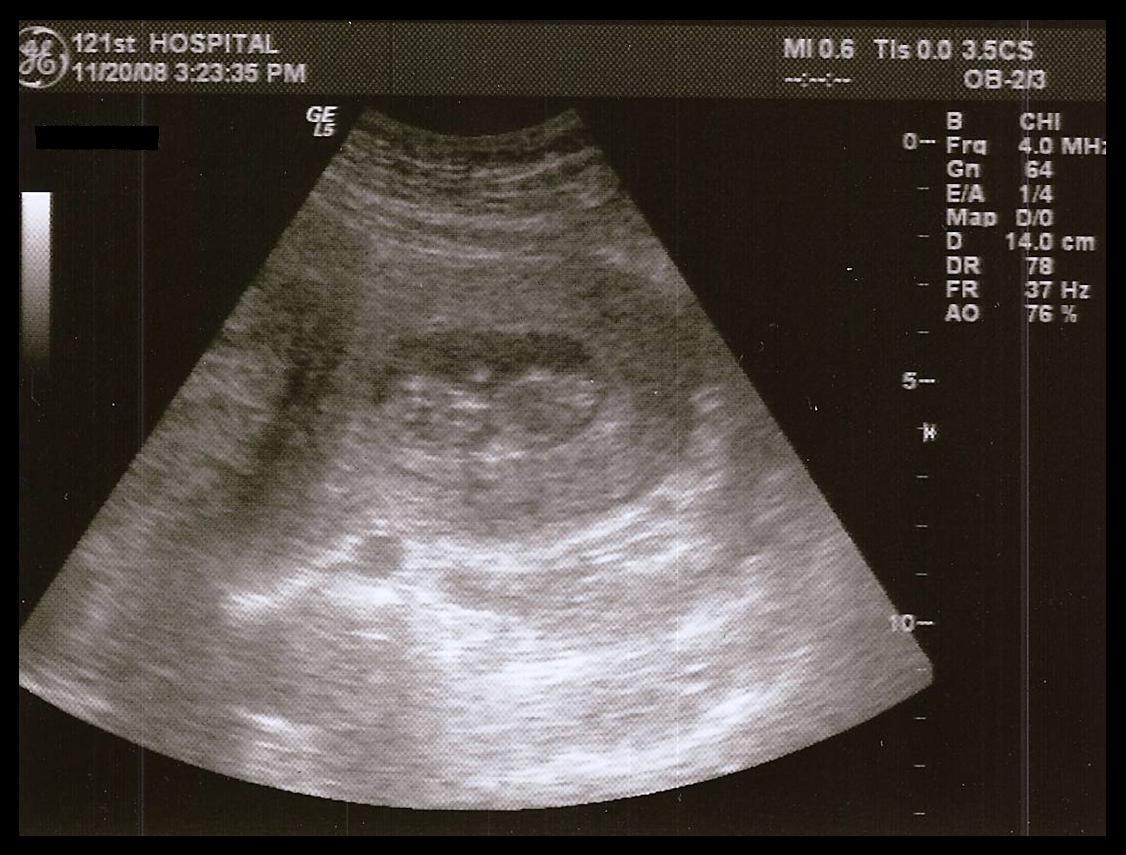

The appointment today went well. As we had figured, I am at just a day or two past 11 weeks, which was even confirmed exactly with the ultrasound. The doctor kept saying how big the fibroid I have is but how it's a "good kind" because it's on the outside of the uterus so, compared with the other possible locations (inside or within the uterine wall), it should cause few problems. His only big concern was whether it might affect the actual delivery, which, obviously, we won't know until we get there.

Paul got there toward the end of the examination, but the doctor did another quick ultrasound so that he could see our little peanut (as I have lovingly termed the image on our ultrasound printoff) and hear the heartbeat, which I already had. We also could see the tiny little heart beating. It was amazing. And this is wonderful news that the heartbeat was so strong because studies have shown that as soon as they can hear the heartbeat with Doppler, then the risk of miscarriage drops dramatically. Paul's been trying for a couple of weeks to hear it with his stethoscope, but hasn't had any luck yet, which isn't surprising since everything I've read says it's about 20 weeks before you can hear the heartbeat that way. Still, he keeps trying every week or so.

And finally, I will leave you tonight with a view of 11 weeks from a slightly different perspective...

It's just that tiny little peanut toward the top that looks like it's waving.